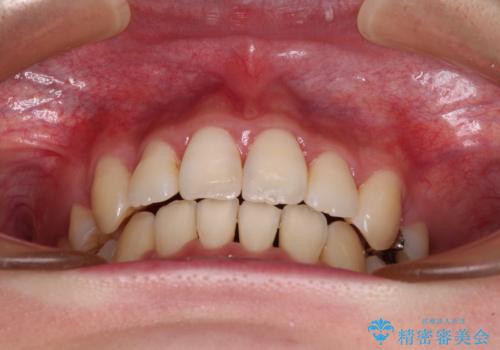

- 前歯の叢生と八重歯を気にして来院された患者様です。

叢生が強く、奥歯の咬合も左右差が大きかったため、上下左右4本を抜歯して、ワイヤー矯正を行うこととしました。

20歳前後と年齢が若かったため、非常にスムーズに歯列が整い、1年半をかけずに治療を終えることができました。